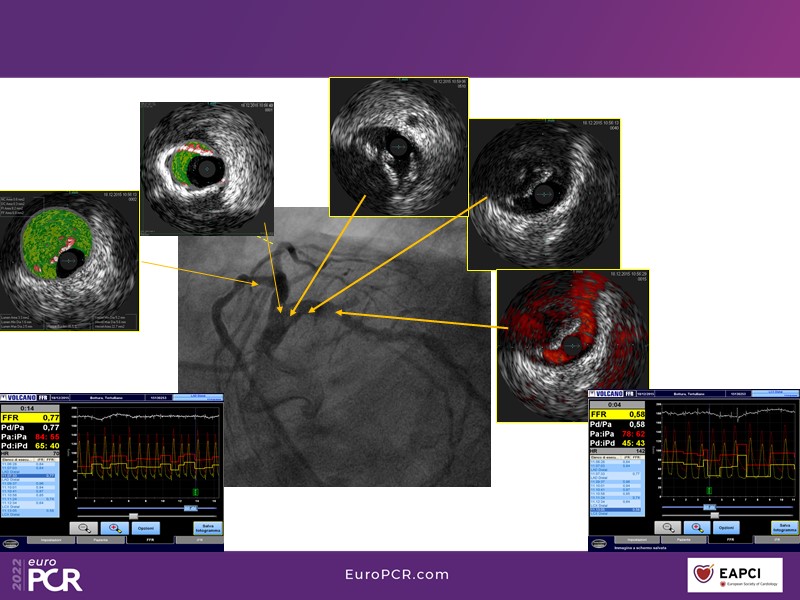

Low contrast complex PCI in a severely calcified lesion: the right tools and techniques

In this session, you will learn how to perform an IVUS-guided low contrast PCI in patients with chronic kidney disease. Discover how to safely and effectively overcome wiring challenges in calcified tortuous coronaries and learn about the proper atherectomy device selection in challenging anatomies.

- To learn how to perform an IVUS-guided low contrast PCI in patients with chronic kidney disease

- To showcase how to safely and effectively overcome wiring challenges in calcified tortuous coronaries